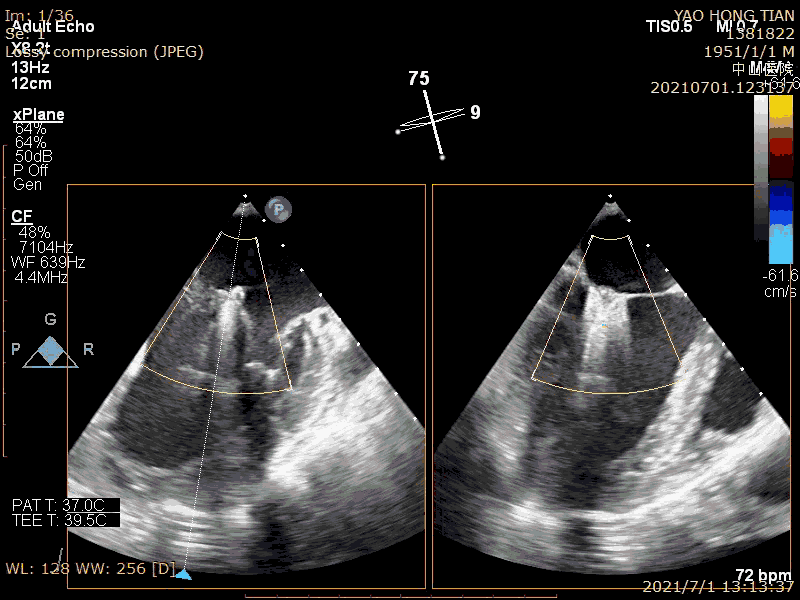

患者,男,70岁。术前超声诊断:左心室射血分数 LVEF 58%,左心室舒张末内径LVDD 52mm,左心房内径LAD 57mm,PASP 63mmHg,二尖瓣瓣尖错位导致重度二尖瓣反流,VC 6*13mm,反流面积19.8cm²(图1-2)。

术前大量反流(VC 6*13mm)

瓣尖错位导致A2P2大量反流